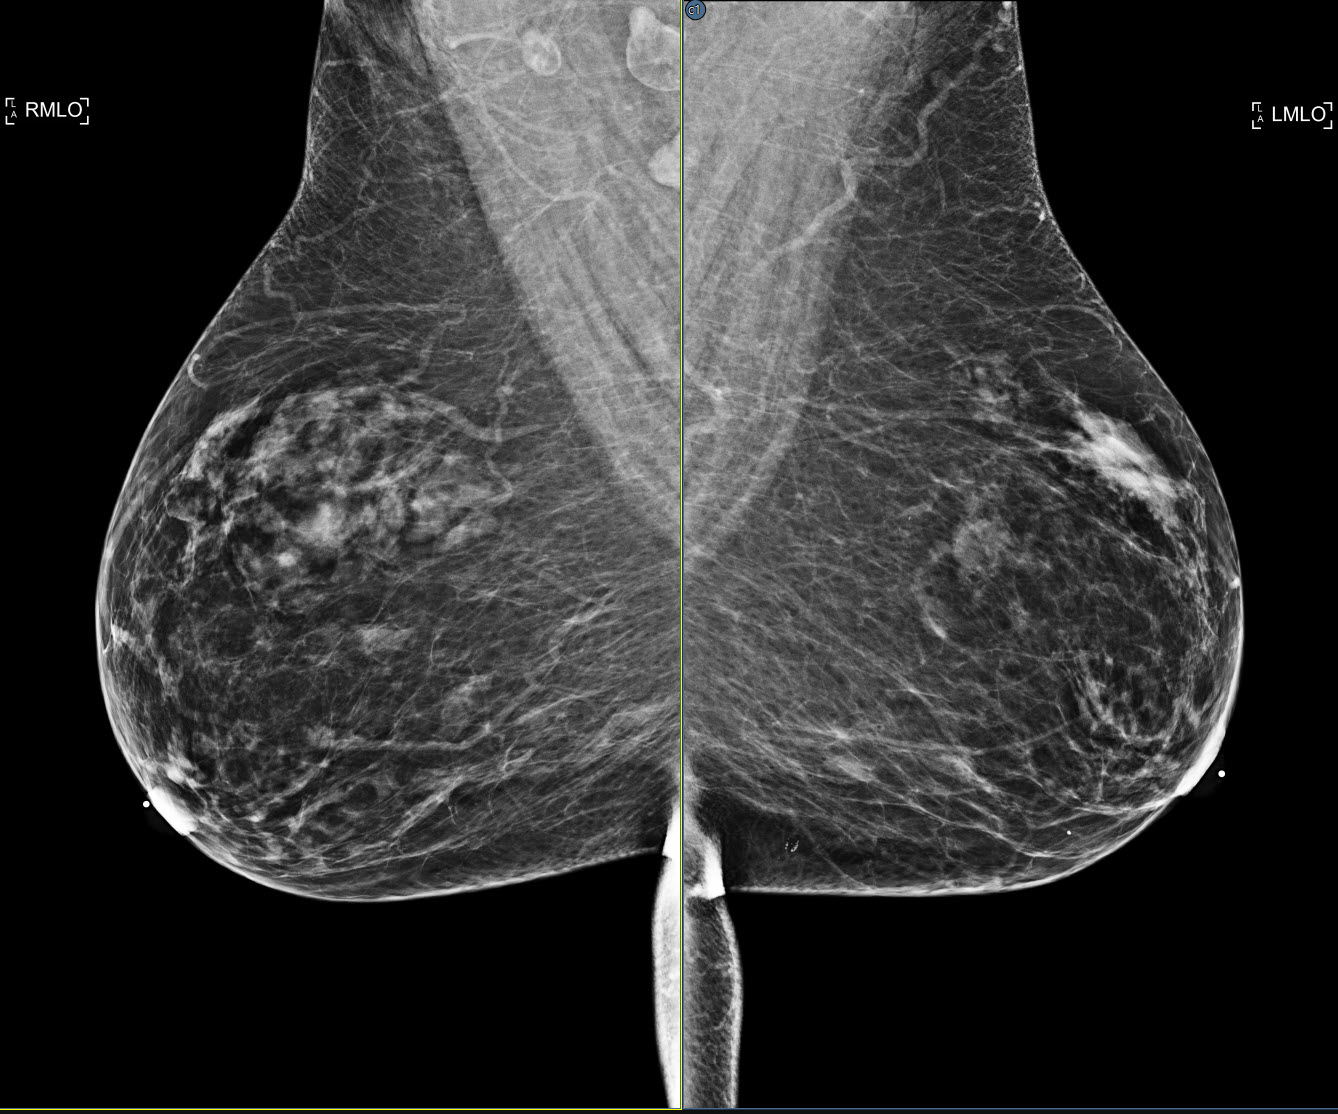

A new setting that enhances the viewer's SmartFit zoom capability by identifying anatomy that is not breast and excluding it from the normal SmartFit calculations. The data remains available by panning the image. The setting is disabled by default. The feature can be enabled from the Enhanced Smart Fit setting in the Images/Zoom section of the viewer settings panel. See Images

| Enabled | Disabled |

![]() |